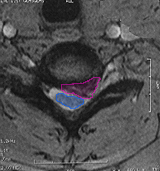

CervicalHernia4

Κήλη αυχενικού μεσοσπονδυλίου δίσκου (φούξια πλαίσιο), με στένωση του νευρικού τρήματος  και πίεση του εξερχόμενου νεύρου.